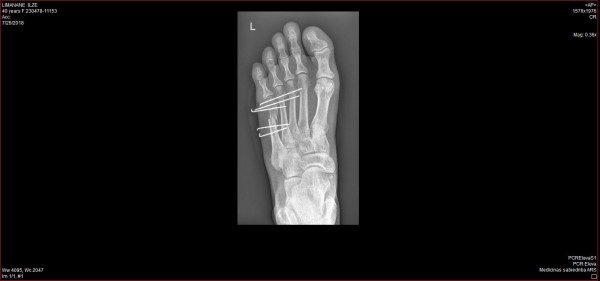

Esam nonākuši līdz pirmajai kļūdai – neej ārā no ārsta kabineta, ja kaut ko nesaproti! Man nav neviena pārmetuma, ko veltīt medicīnas nozares darbiniekiem, jo savā atveseļošanās procesā saņēmu lielisku aprūpi visās medicīnas iestādēs, ko nācās apmeklēt. Tomēr neviens dakteris nevar uzminēt to, ka man kaut kas nav skaidrs, ja to nepajautāju, bet visu laiku māju ar galvu. Par laimi šo kļūdu, kā jau iepriekš minēju, veiksmīgi laboju ar zvanu savai kolēģei. Tagad es zinu, ka šāda operācija ir jāveic vai nu uzreiz (pirmo 24 h stundu laikā) vai kad tūska ir nogājusi, tātad teorētiski varēju to darīt arī pēc Jāņiem. Tā kā man gribējās pēc iespējas ātrāk sākt atveseļoties, tad jau plkst. 16:00 esmu Gaiļezera uzņemšanā un 19:00 jau uz operāciju galda. Operācija ilgst tieši tik, cik man vajag pusmaratona noskriešanai jeb nedaudz zem 1:40h. Tieku pie 5 jauniem pīrsingiem – jā, man no pēdas ārā spīd pieci glīti āķīši, kas nozīmē, ka turpmākās 5 nedēļas nedrīkstēšu kāju pakļaut samērcēšanai un būs jāveic pārsiešana divas reizes nedēļā, jo ievietotās stieples prasa ļoti rūpīgu kopšanu. Ķirurgs sola, ka pēc nedēļas varēšu nomainīt langeti pret speciālu kurpi, kas slogos kājas pēdu tā, ka varēšu saudzīgi staigāt, nenoslogojot lauzto vietu, bet saglabājot iešanu, kas nozīmē, ka nezudīs muskuļu funkcionalitāte.

Stieples, kas palīdz kauliņa saaugšanai

Piecu nedēļu kaulu saaugšanas periods bija beidzies, un es devos pie ķirurga izņemt savus “pīrsingus”. Izrādās, ka tas notiek bez anestēzijas, bet zināju, ka man ir augsts sāpju slieksnis. Galu galā izrādās, ka biju vairāk sabiedēta nekā tas bija nepieciešams. Man procedūra pārāk nemaz nesāpēja, bija tikai jocīgi, ka izvelk tādus garus kātiņus no pēdas. Kontrolrentgens parādīja, ka viss ir kārtībā, lai gan nedaudz bija nobīdes no gribētā, bet nekas daudz, tā kā varēja teikt, ka esmu labi uzvedusies un stieples neesmu izkustinājusi no vietas. Pēc pusotras nedēļas bija jāsāk staigāt.